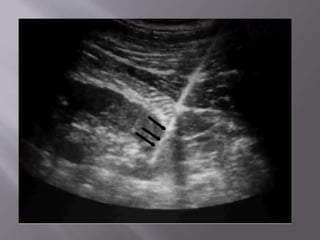

Here we clearly see free fluid in Morrison's pouch that extends

superiorly around the liver

See the needle entering the peritoneal cavity obliquely from just

beneath the indicator marker.